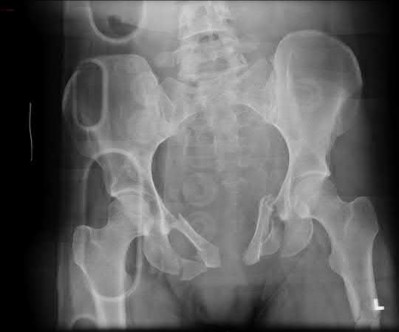

A 35 year-old female presents after prolonged extrication from a motor vehicle collision complaining of severe pelvic pain. Physical examination reveals diminished perianal sensation. She is otherwise neurologically intact. Figures A through D are radiographs and representative CT cuts of her injury. Which of the following nerve roots has likely been injured by the acute trauma?

The clinical scenario is consistent with a high-energy sacral fracture. The radiographs in figures A and B demonstrate a sacral fracture with posterior displacement of the right hemipelvis seen on the inlet view. Figures C and D are axial and sagittal CT images which show a displaced fracture of the right

hemisacrum along with a transvere fracture component through the S3 body . Diminished perianal sensation is concerning for an S2 nerve root injury.

Mehta et al reviewed the current management of sacral fractures. They note that the S1 and S2 nerve roots are more likely to be injured with sacral fractures as they occupy 1/3 to 1/4 of the neural foramina, as opposed to S3 and S4, which only occupy 1/6 of the neural foramina.

Robles reviewed the current literature to ascertain principles of evaluation and treatment for transverse sacral fractures. The author notes that injury to nerve roots S2 to S5 is manifested by impairment of urinary and anal continence and sexual function.